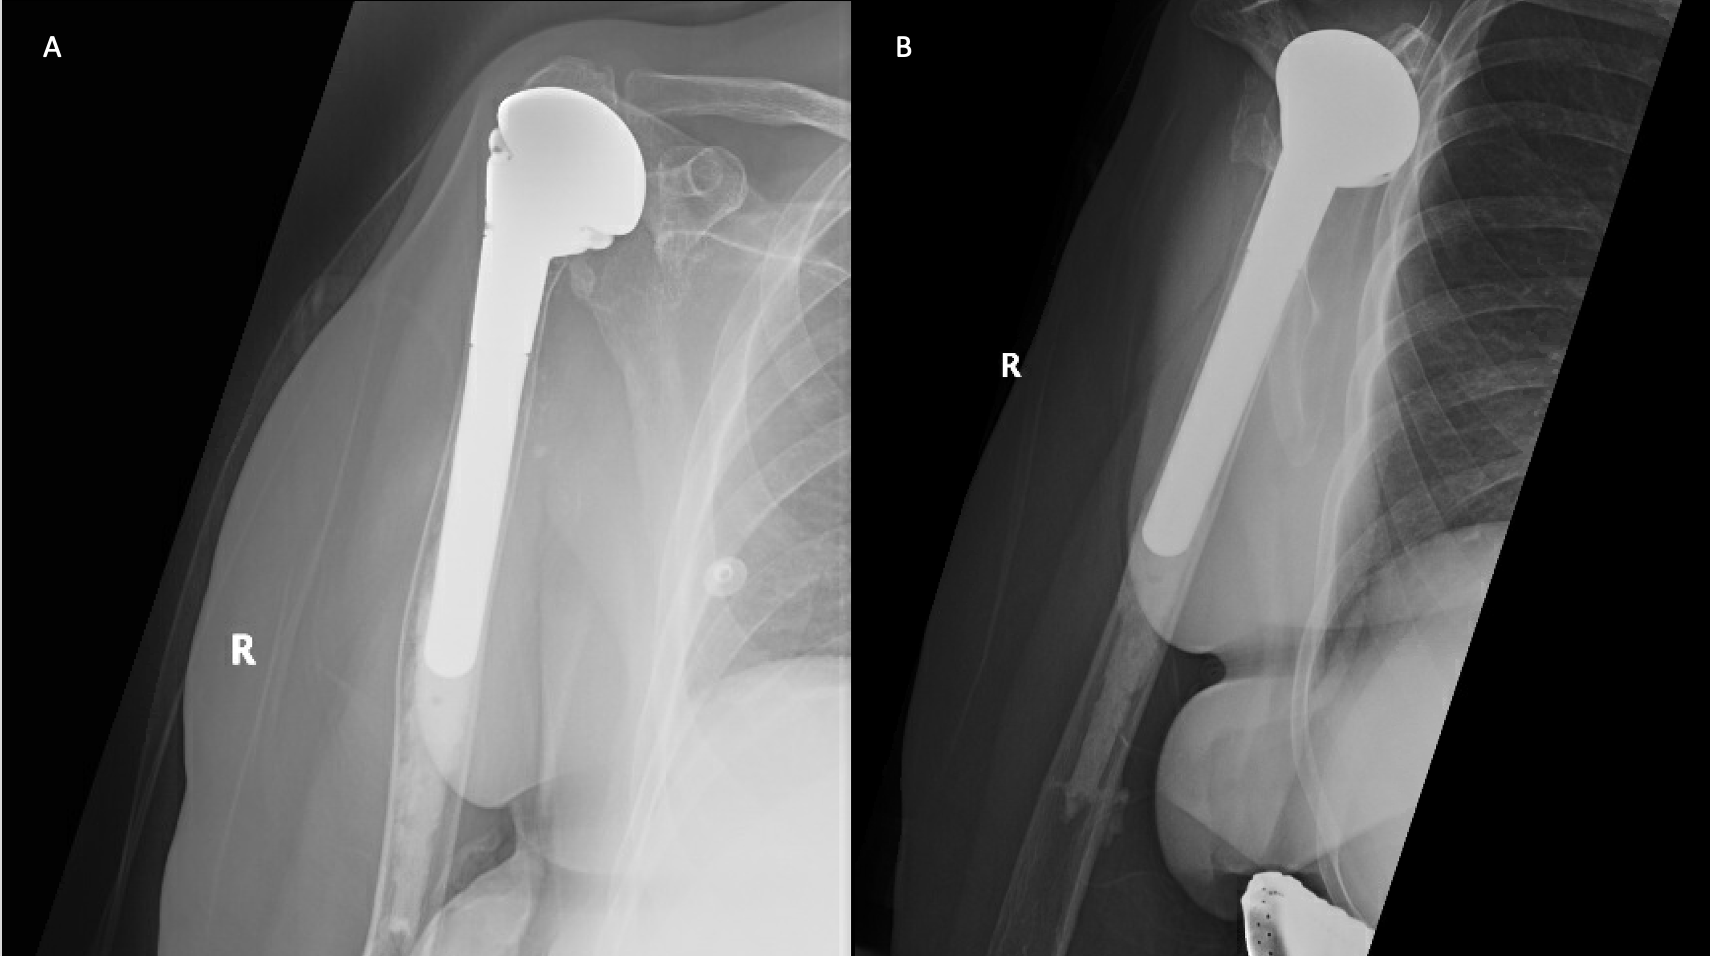

A 69-year-old woman presented after resection arthroplasty of her right shoulder hemiarthroplasty and completion of antibiotic treatment for culture negative PJI for evaluation of reconstructive options. She had a history of a displaced two-part right proximal humeral fracture which was repaired with an intramedullary nail. Post operatively, she had persistent pain and CT scan of the shoulder showed two screws in the humeral head that extended through the cortex and into the glenohumeral joint. The screws were removed and replaced with smaller screws. Subsequently, she had non-union of the fracture in the setting of deltoid weakness and was revised to a right hemiarthroplasty (Figures 1-3). Post operatively, she had persistent pain refractory to physical therapy and diminished function that was impacting her quality of life. She sought subsequent care, and there was concern for arthroplasty failure secondary to a septic versus aseptic condition and the decision to proceed with resection arthroplasty was made. During resection arthroplasty, a significant amount of fluid was expressed from the joint space. The combination of the clinical picture of progressive and persistent pain and the gross expression of fluid were concerning for PJI and the decision to treat was made. It was felt that the extent of humeral bone loss did not allow for a stable cement spacer, so none was placed. Intraoperative joint fluid cultures, anaerobic, and fungal cultures were all negative for growth. Cultures were held for 21 days to rule out C. Acnes infection. Considering the plan for future reimplantation, infectious disease consultation recommended a 6-week course of vancomycin but after 2 days the patient had a transfusion reaction and was switched to daptomycin. She was left with markedly limited active motion associated with severe pain. After completion of the antibiotic course, the patient elected to proceed with revision surgery. This patient had a flattened and distorted glenoid and atrophied rotator cuff musculature demonstrated prior to resection arthroplasty on CT (Figure 4). This patient’s prior hemiarthroplasty had been a tantalum coated, cemented humeral stem with associated marked thinning of the humeral cortex even prior to resection arthroplasty, and this resulted in a large amount of proximal humeral bone loss during the resection (Figure 5). The patient was severely debilitated by the right shoulder and wanted to proceed with reconstruction. Because of the combination of glenoid and humeral bone loss and the lack of rotator cuff attachments, a custom constrained prosthesis design process was initiated, and the implant was available 16 months after the resection arthroplasty. Preoperative 3 phase SPECT (Single Photon Emission Computed Tomography) three phase bone scan, upper extremity CT, and blood work (WBC 5.4, ESR 9, CRP 0.8) showed no suggestion of active infection.

A 62-year-old woman presented for evaluation of her reconstructive options after resection arthroplasty of a right rTSA and completion of antibiotic treatment for culture negative PJI. Her rTSA had been an Encore prosthesis placed due to rotator cuff arthropathy (Figures 6). Post-operatively she had persistent pain, stiffness, and tenderness to palpation that was treated with physical therapy, a steroid injection, and manipulation under anesthesia. An infectious work up due to the chronic and persistent nature of the pain showed WBC 7.4, ESR 53, CRP 1.2. Patient denied further work up with a tagged white cell scan and preferred continued clinical monitoring to observe pattern of symptoms. Eleven months later, she endorsed persistent pain. Repeat infectious work up showed WBC 4.5, ESR 13, and CRP 1.1. Despite the normal inflammatory markers, a 10-day trial of Augmentin was initiated and failed to change her symptoms. The decision to proceed with 1 vs 2 stage reconstruction was made. During resection arthroplasty, a substantial amount of fluid was expressed from the joint capsule concerning for PJI. A cement spacer was placed, and the patient was treated with 6 weeks of vancomycin and cefepime (Figure 7). There was proximal humeral bone loss as the result of resection arthroplasty due to the humeral stem. The glenoid component was loose and associated with glenoid bone loss, further complicated by the need for removal of a broken central screw (Figure 8).

Intra-operative frozen sections, tissue cultures, and gram stain showed no signs of infection. Following treatment, inflammatory markers remained normal (WBC 5.5, ESR 22, CRP 0.9), and aspiration of the shoulder showed no organisms on gram stain and no growth on aerobic, anaerobic, fungal, and acid-fast bacilli cultures. Cultures were held for 21 days to rule out C. Acnes infection. She was left with profoundly limited active motion and severe pain and the patient elected to proceed with revision surgery. Because of the combination of severe glenoid and humeral bone loss and the lack of rotator cuff attachments necessitating a design with additional constraint, the decision to proceed with custom prosthesis design was made 9 weeks after resection arthroplasty.